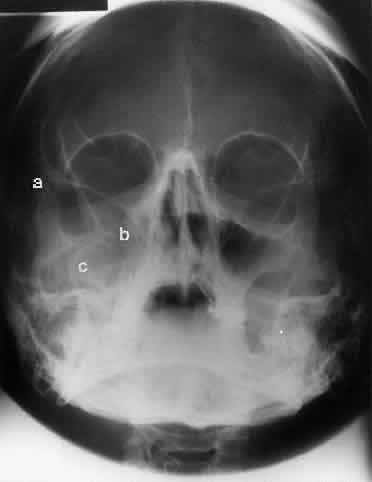

The posterior segment of the lateral wall courses posterior medially and can be seen in anterior projections such as the Caldwell view. This view allows direct visualization of the greater sphenoid wing contribution to the lateral wall. Bone density changes in the greater wing of the sphenoid, such as from a meningioma, can be detected. Fractures of the lateral orbital wall can occur from blunt trauma to the malar prominence. The zygomatic complex fracture (tripod) results from separation of the zygomatic-frontal, zygomatic-temporal, and the zygomatic-maxillary sutures. These fractures are associated with an inferior displacement of the malar prominence and a rounded lateral canthus (Figs. 8 and 9).

Fig. 8. A zygomatic complex fracture (tripod) after blunt trauma to the right cheek. Note the right zygoma is inferiorly displaced. (a, zygomatic-frontal suture separation; b, orbital rim disruption; c, opacification of maxillary sinus)